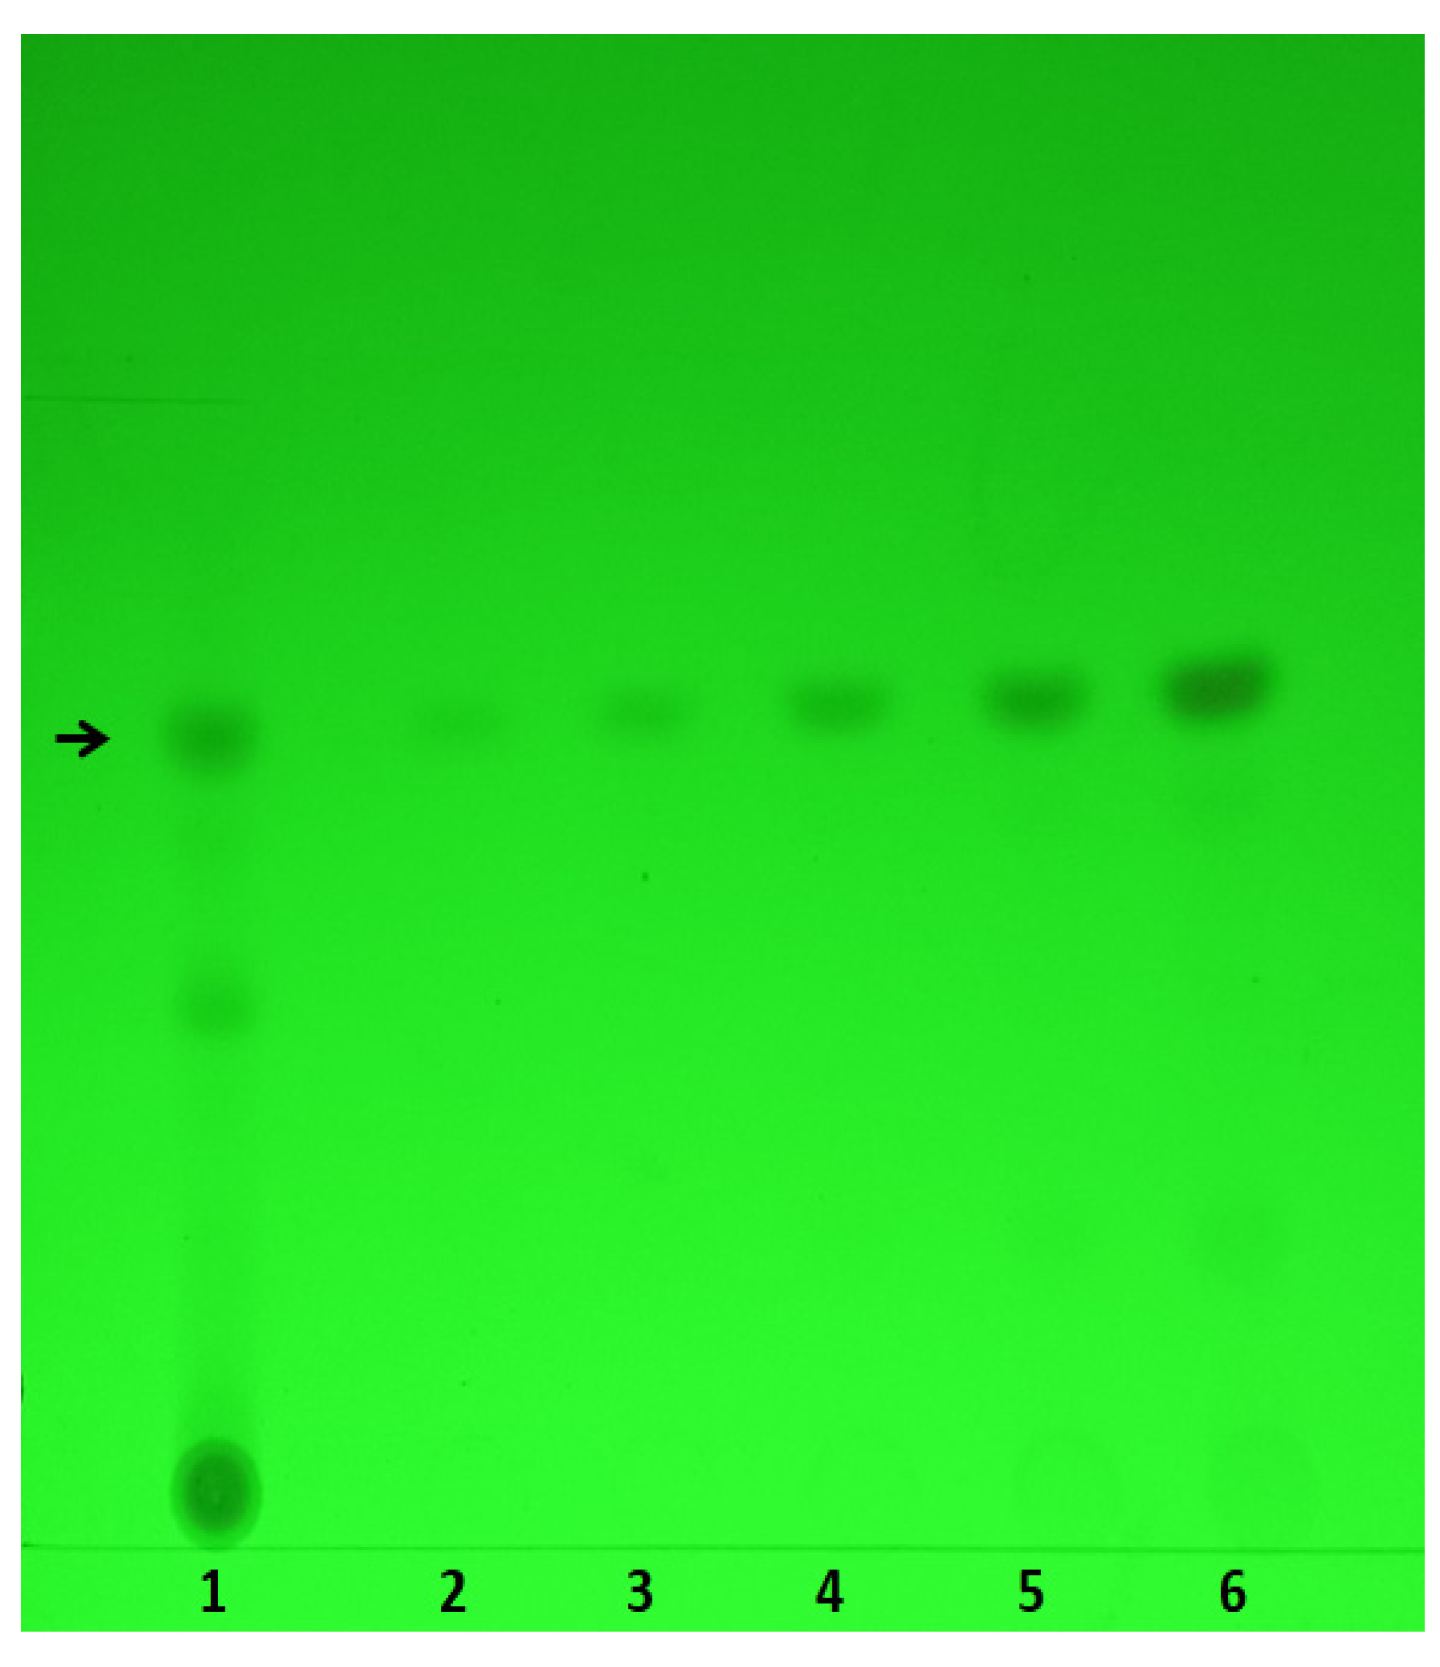

4.5. Tanshinone IIA, and S. miltiorrhiza Root Ethanolic Extract